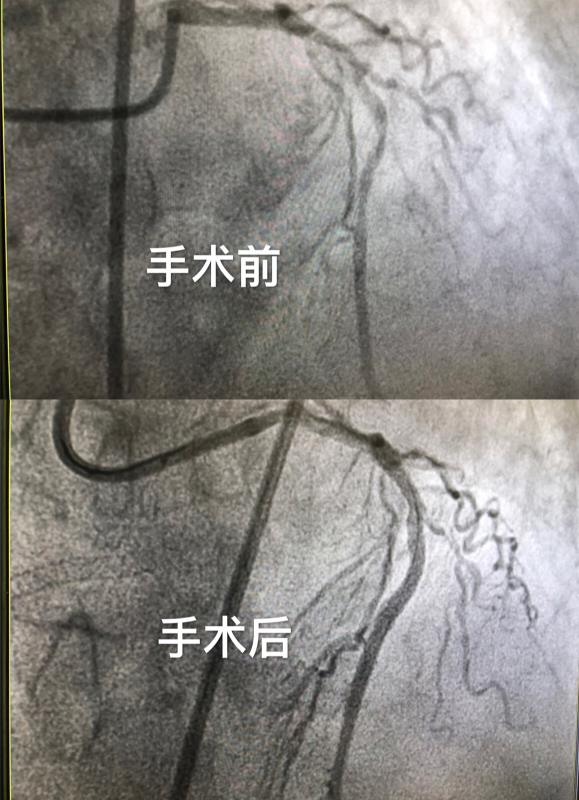

7月17日,医务人员为患者进行冠脉造影,结果显示患者冠脉三支严重病变。因为患者心功能极差,无法耐受长时间介入手术,该院袁祖贻副院长、白玲主任、王燕妮教授、闫炀教授、刘平教授专家团队反复讨论治疗方案,大家一致认为心力衰竭由严重心肌缺血诱发,只有尽快开通闭塞血管,才能最大程度挽救缺血心肌,否则患者随时会有生命危险。但患者心肺功能差,不能平卧,无法耐受长时间介入手术。一边是生的希望,一边是直面死神,经过心内心外专家团队的认真讨论及评估,大家决定在ECMO(体外膜肺氧合)支持下拼力一搏、全力以赴为病人争取生的机会。家属也被医务人员不放弃的精神感动,迅速同意签字。

一场生死之战拉开序幕,经过袁祖贻副院长带领的心血管医疗团队的全力抢救,在心内科、心外科、介入手术室、麻醉科等多科室通力协作下,患者成功开通冠脉血管,缺血心肌得到最大程度改善,目前在监护病房继续进一步治疗。